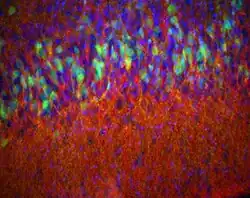

![]() Córtex piriforme de um rato D2-eGFP (verde) de 14 dias com corante manchado para encefalina (vermelho) e DAPI (azul) para mostrar núcleos. Epifluorescência.